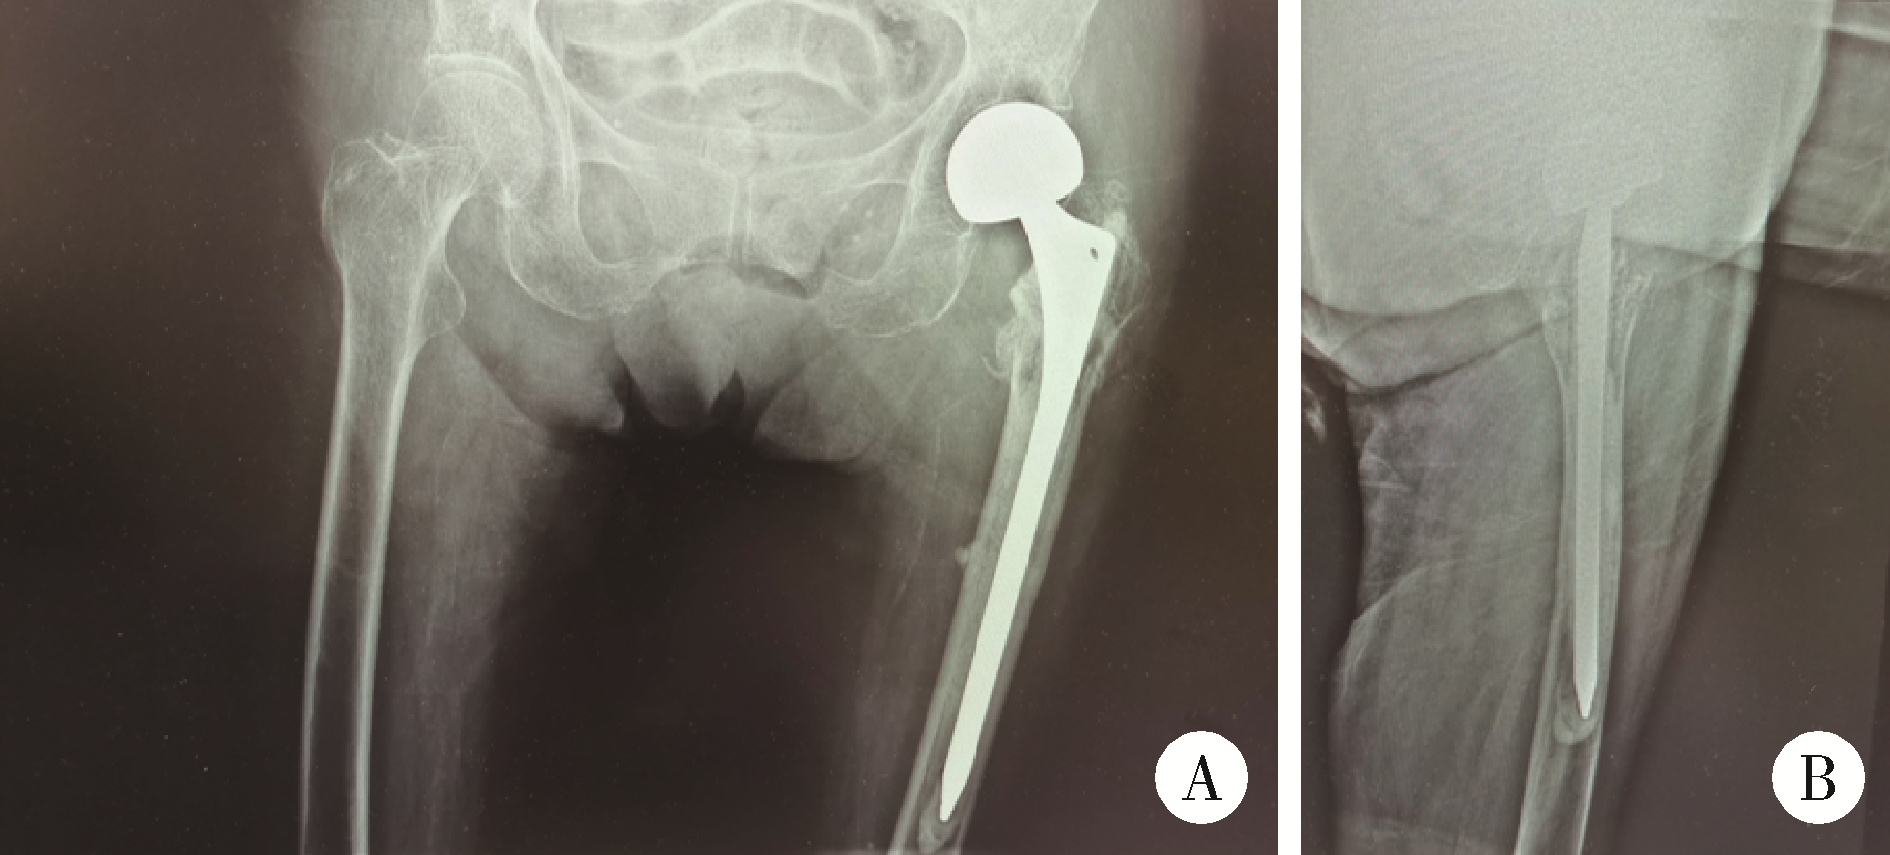

图6 患者左侧半髋关节置换术后X线片

Figure 6 X-ray films of patient after left hemiarthroplasty

A, X-ray films of both hips; B, left hip lateral view, post-left hip hemiarthroplasty.